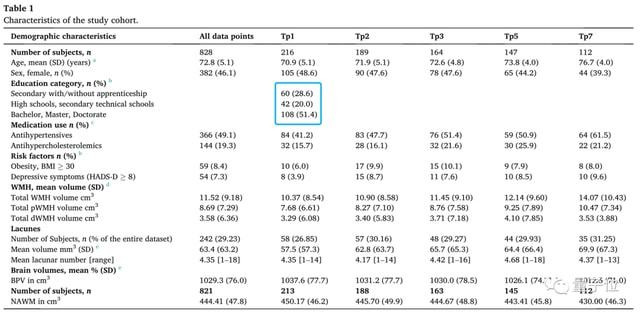

在此基础上,研究人员针对200多位智力水平正常的老人,展开了为期7年的跟踪调查。

他们定期使用核磁共振成像来扫描实验对象大脑,并对其心理健康密切关注。

其中,高中以下学历背景的老人有60位,高中或高职学历背景的老人有42位,大学及以上学历背景的老人有108位。

总体来看,调查7年内脑白质高信号(WMH)显著增加,平均每年增长量为7.9%。